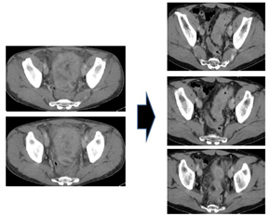

治療開始から9週(3コース)経過後CT所見で原発巣縮小を確認(PR) |

治療開始から19週(6コース)経過後CT所見で原発巣は縮小継続しているが 多発肝転移が出現 |